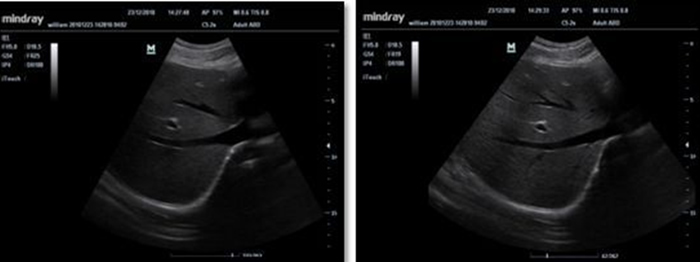

Sample Clinical Images